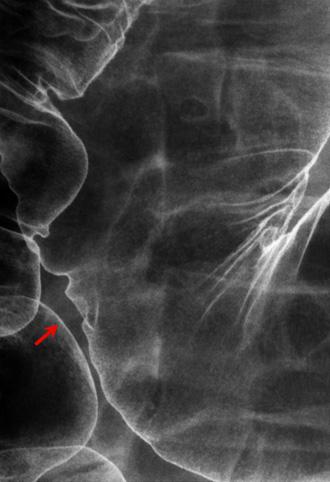

질환(병리주체)의 분류 종양양 병변/정맥괴

부위(장기별) 대장/횡행

검사방법 X-P

종양의 최대경(밀리미터) 30~34